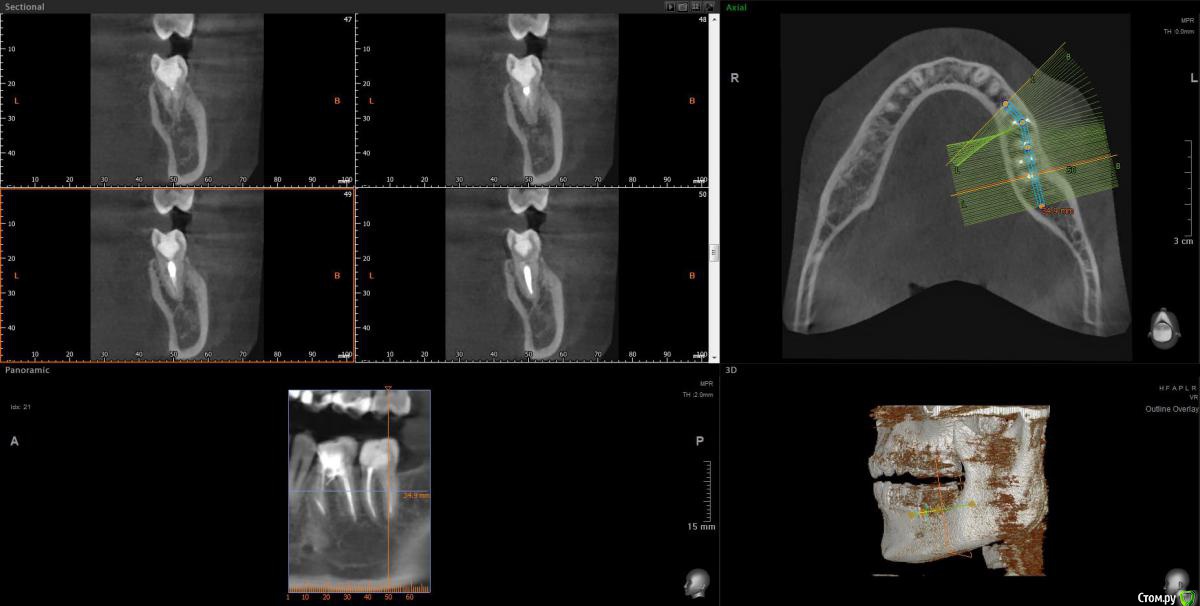

Vords Опубликовано 11 июня, 2020 Поделиться Опубликовано 11 июня, 2020 (изменено) Доброго вечера, профессионалы. Прошу у Вас помощи. Буду очень благодарен за консультацию. 3 недели назад появились боли в в жевательных зубах (около 37 и 36 зубов). В виду того, что боли были достаточно серьезные, а врач, у которого я лечился ранее не мог меня принять из-за пандемии - пришлось идти в городскую поликлинику. По результатам похода был поставлен диагноз пульпит 37 и глубокий кариес 36. На 36 поставили пломбу - 37 успешно депульпировали. На этом история 37 зуба закончена. С 36 после постановки пломбы начались дикие ночные боли и боли при накусывании. На повторном приеме был поставлен диагноз пульпит 36 - поставлено лекарство для умертвления нерва. После этого боль при накусывании прошли. В следующий прием пришел на чистку каналов и пломбировку. Во время этой процедуры я вдруг ощутил совершенно дикую боль (как выяснилось потом - в этот момент и произошла перфорации в области фуркации). Врач ничего не сказал - просто поставил метапекс и запломбировал каналы. В этот момент начались боли при накусывании. а потом постоянная тянущая боль. Продолжалось это около 3 дней - я пошел в другую стоматологию где мне сделали рентген и с подозрение на перфорацию отправили на КТ. По результатам КТ перфорация была подтверждена. С КТ я пришел в городскую стомотологию где мне предложили закрыть перфорацию цементом (pro что-то там - не могу сказать точно). Закрыли ее во вторник на этой неделе. Сегодня восстановили коронку и поставили световую пломбу. Беда в том, что боль при накусывании и "нытье" с этой стороны так и не прошли. По словам стомотолага гос клиники - боль при накусывании из-за метапекса и когда он рассосется - боль пройдет. (до 6 месяцев). Я прилагаю рентген (ужасное качество), фото КТ и ссылку в облако на КТ. Я допускаю, что никто не захочет лезть в облако и тратить свое время на просмотр на КТ (сам не могу разобраться с программой, что бы сделать достойные скрины), но если вдруг у кого-то найдется время - буду очень благодарен. Рентген сделан сразу после пломбировки канала. КТ через 3 дня после этого. В связи с этим вопрос. Возможно ли, что боль при надавливании пройдет если подождать пока рассосется метапекс или это пустая трата времени? Мне стоит ждать какое - то время или в этой ситуации мне поможет только удаление? Благодарю Вас за уделенное время Ссылка на КТ https://cloud.mail.ru/public/44WE/2JeTfXmr2 Изменено 11 июня, 2020 пользователем Vords Ссылка на комментарий

krokomot Опубликовано 11 июня, 2020 Поделиться Опубликовано 11 июня, 2020 Судя по всему у вас в 6м зубе выведен не только метапекс но и гуттаперчевый штифт, скорее всего, если это не исправить боли сохранятся, и что там с коронкой не понятно, на кт сильные тени из-за большого объема рентгеноконтрасного материалла, а прицельный снимок что вы сделали, сделан не поп правилам и на нем сильные искажения, понять трудно что с коронкой. Короче, зуб с перфорацией , выведенным материалом за апексом и гуттаперчей, и при этом еще и беспокоит, прогноз сомнительный. возможно всё можно переделать и всё станет нормально , но это не точно. Вам нужен грамотный доктор эндодонтист. 1 Ссылка на комментарий

wladdX Опубликовано 11 июня, 2020 Поделиться Опубликовано 11 июня, 2020 (изменено) Скриншоты Изменено 11 июня, 2020 пользователем wladdX 1 Ссылка на комментарий

Vords Опубликовано 11 июня, 2020 Автор Поделиться Опубликовано 11 июня, 2020 (изменено) WladdX, огромное спасибо Вам за потраченное на скрины время. А то я так и не смог освоить эту программу (рукалицо). У меня даже есть ощущение, что я вижу теперь штифт, о котором говорил krokomot (хотя и не факт)))) Изменено 11 июня, 2020 пользователем Vords Ссылка на комментарий